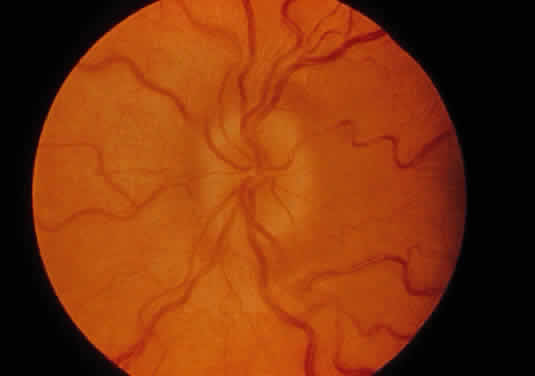

Corneal clouding (Fig. 10), hyperopic astigmatism, and a mild retinopathy with surface-wrinkling maculopathy (Fig. 11) appear to be the constant ocular triad.75 Some patients have retinal vascular tortuosity, optic nerve head swelling (Fig. 12), visual field defects, and abnormalities in color vision. Visual complaints are uncommon.

Fig. 11. Surface-wrinkling maculopathy in a patient with mucolipidosis III. (Traboulsi E, Maumenee I: Ophthalmologic findings in mucolipidosis III. Am J Ophthalmol 102:529, 1986)